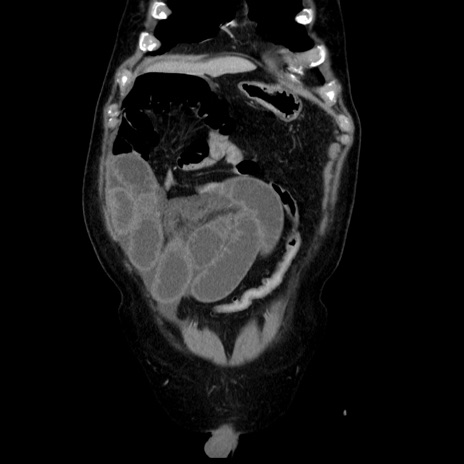

症例30(冠状断像)

【症例】80歳代男性

【主訴】臍周囲痛

【現病歴】約6時間前から臍下部痛が出現。次第に腹部膨隆・背部痛も生じてきたため来院。背部痛の場所は変化しない。

【身体所見】意識清明、BT 36.3℃、BP  131/87mmHg、P 87bpm、SpO2 100%(RA)、臍周囲自発痛・圧痛あり、反跳痛なし、自発痛部位に一致して板状硬あり、腹部膨隆、腸雑音減弱、CVA tenderness両側陰性。

【データ】WBC 19600、CRP 0.33